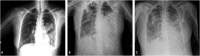

Epidemiology: The most frequent causes of acquired infection in the community that require admission to the ICU are respiratory infections, urinary tract infections and infections of the central nervous system. Among the infections acquired in the ICU, devices-associated infections are the most frequent.

Clinical manifestations: Depends on the location of the infection.